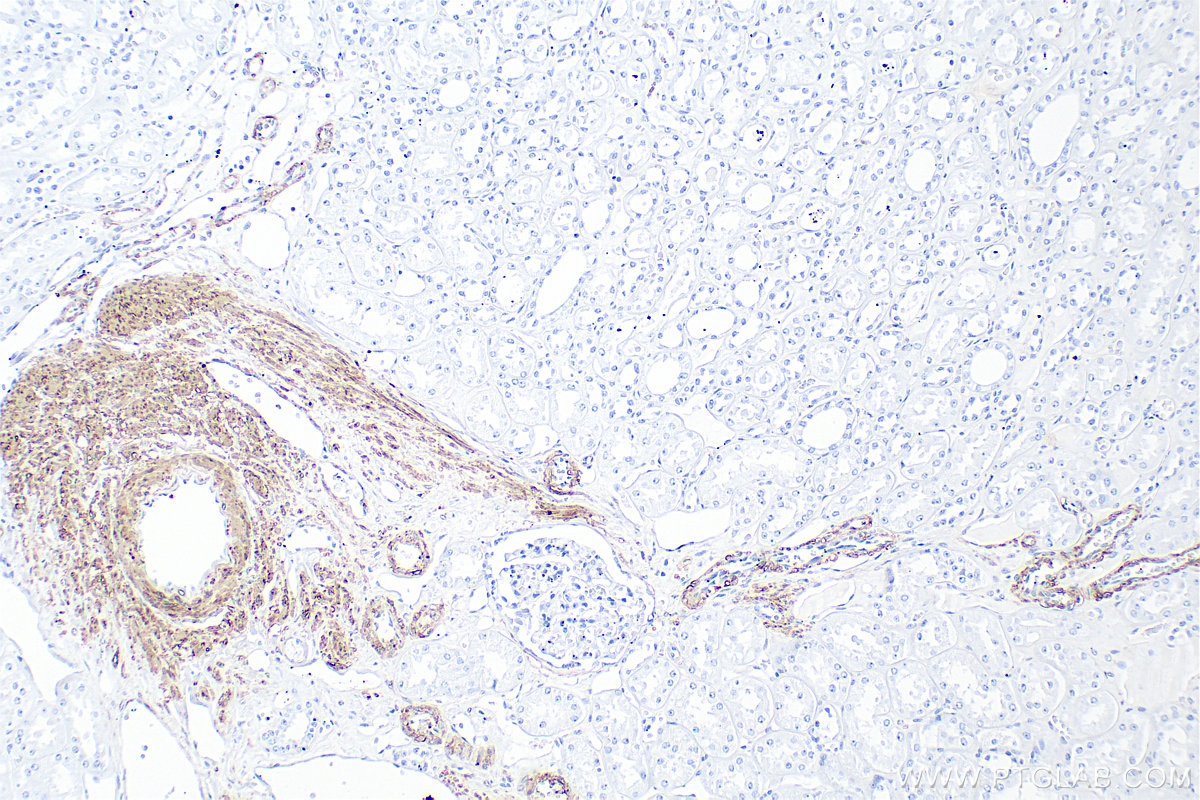

| Positive IHC detected in | mouse heart tissue, human kidney tissue Note: suggested antigen retrieval with TE buffer pH 9.0; (*) Alternatively, antigen retrieval may be performed with citrate buffer pH 6.0 |

| Immunohistochemistry (IHC) | IHC : 1:2000-1:8000 |